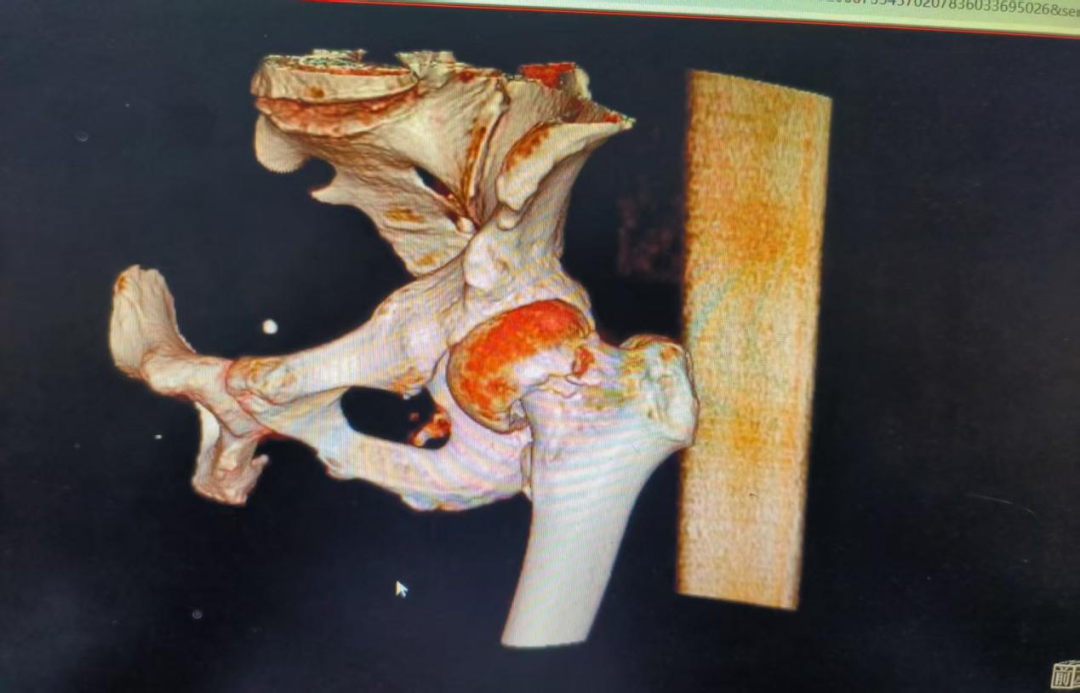

面对这样一位骨折陈旧、全身状况“亮起红灯”的患者,张平带领团队对患者病情进行分析评估及讨论,结合病史、症状、体征及影像检查结果,联合多学科(心血管科、脾胃病科、麻醉科等)全力纠正调理后,将患者身体调理至可耐受手术的最佳状态。

由于患者术前已发生下肢DVT是关节置换术的“红色警报”,有术中术后血栓脱落导致致死性肺栓塞的风险。团队在术前为患者放置了下腔静脉滤器,为手术筑起了“生命护栏”,这是手术得以安全开展的关键前提。术中,张平和团队凭借丰富的复杂关节置换经验,术中精细操作,克服了组织粘连、骨质条件差等困难,为其成功实施人工全髋关节置换术。目前患者恢复良好,已可借助助行器下地行走。